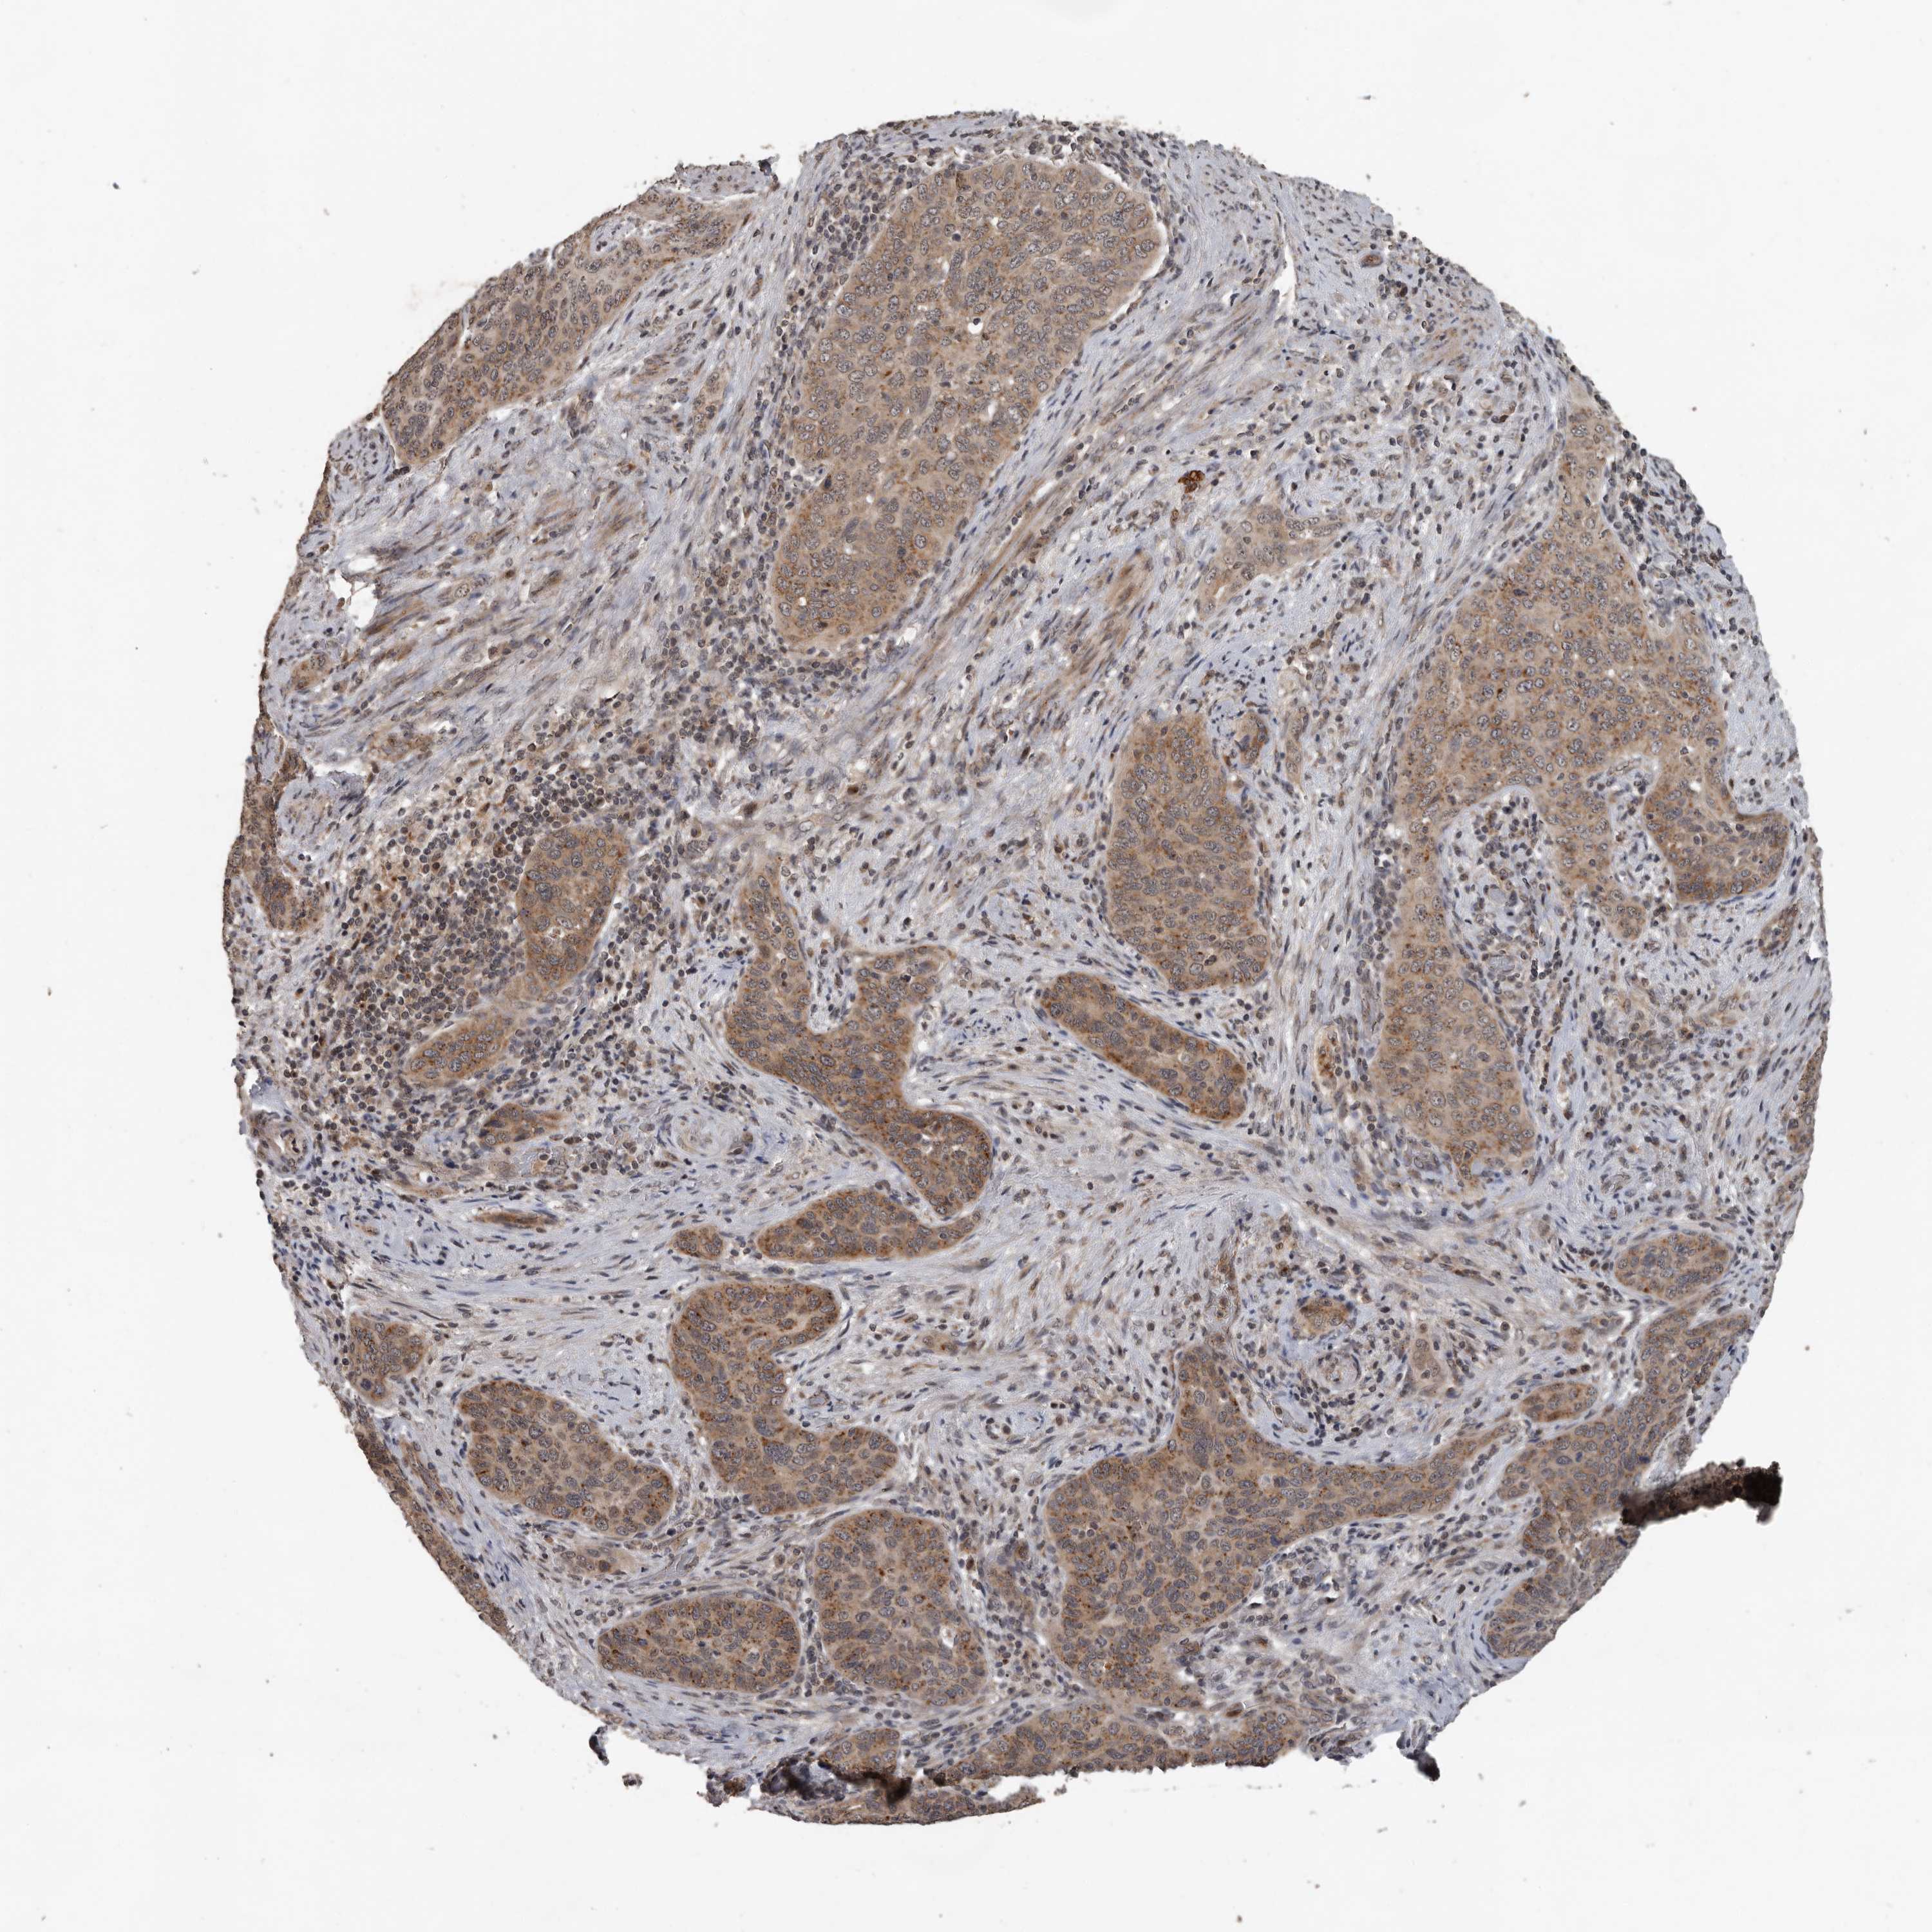

CERVICAL CANCER - Protein expressioni

A mouse-over function shows sample information and annotation data. Click on an image to view it in a full screen mode. Samples can be filtered based on level of antibody staining by selecting one or several of the following categories: high, medium, low and not detected. The assay and annotation is described here.

Note that samples used for immunohistochemistry by the Human Protein Atlas do not correspond to samples in the TCGA dataset.

Antibody stainingi

Antibody staining in the annotated cell types in the current human tissue is reported as not detected, low, medium, or high, based on conventional immunohistochemistry profiling in selected tissues. This score is based on the combination of the staining intensity and fraction of stained cells.

Each image is clickable and will lead to virtual microscopy that enables deeper exploration of all samples and also displays staining intensity scores, fraction scores and subcellular localization as well as patient and tissue information for each sample.

Antibody HPA028355

Antibody HPA028357

Staining

High

Medium

Low

Not detected

Intensity

Strong

Moderate

Weak

Negative

Quantity

>75%

75%-25%

<25%

None

Location

Nuclear

Cytoplasmic/membranous

Cytoplasmic/membranous,nuclear

Squamous cell carcinoma, NOS

Adenocarcinoma, NOS